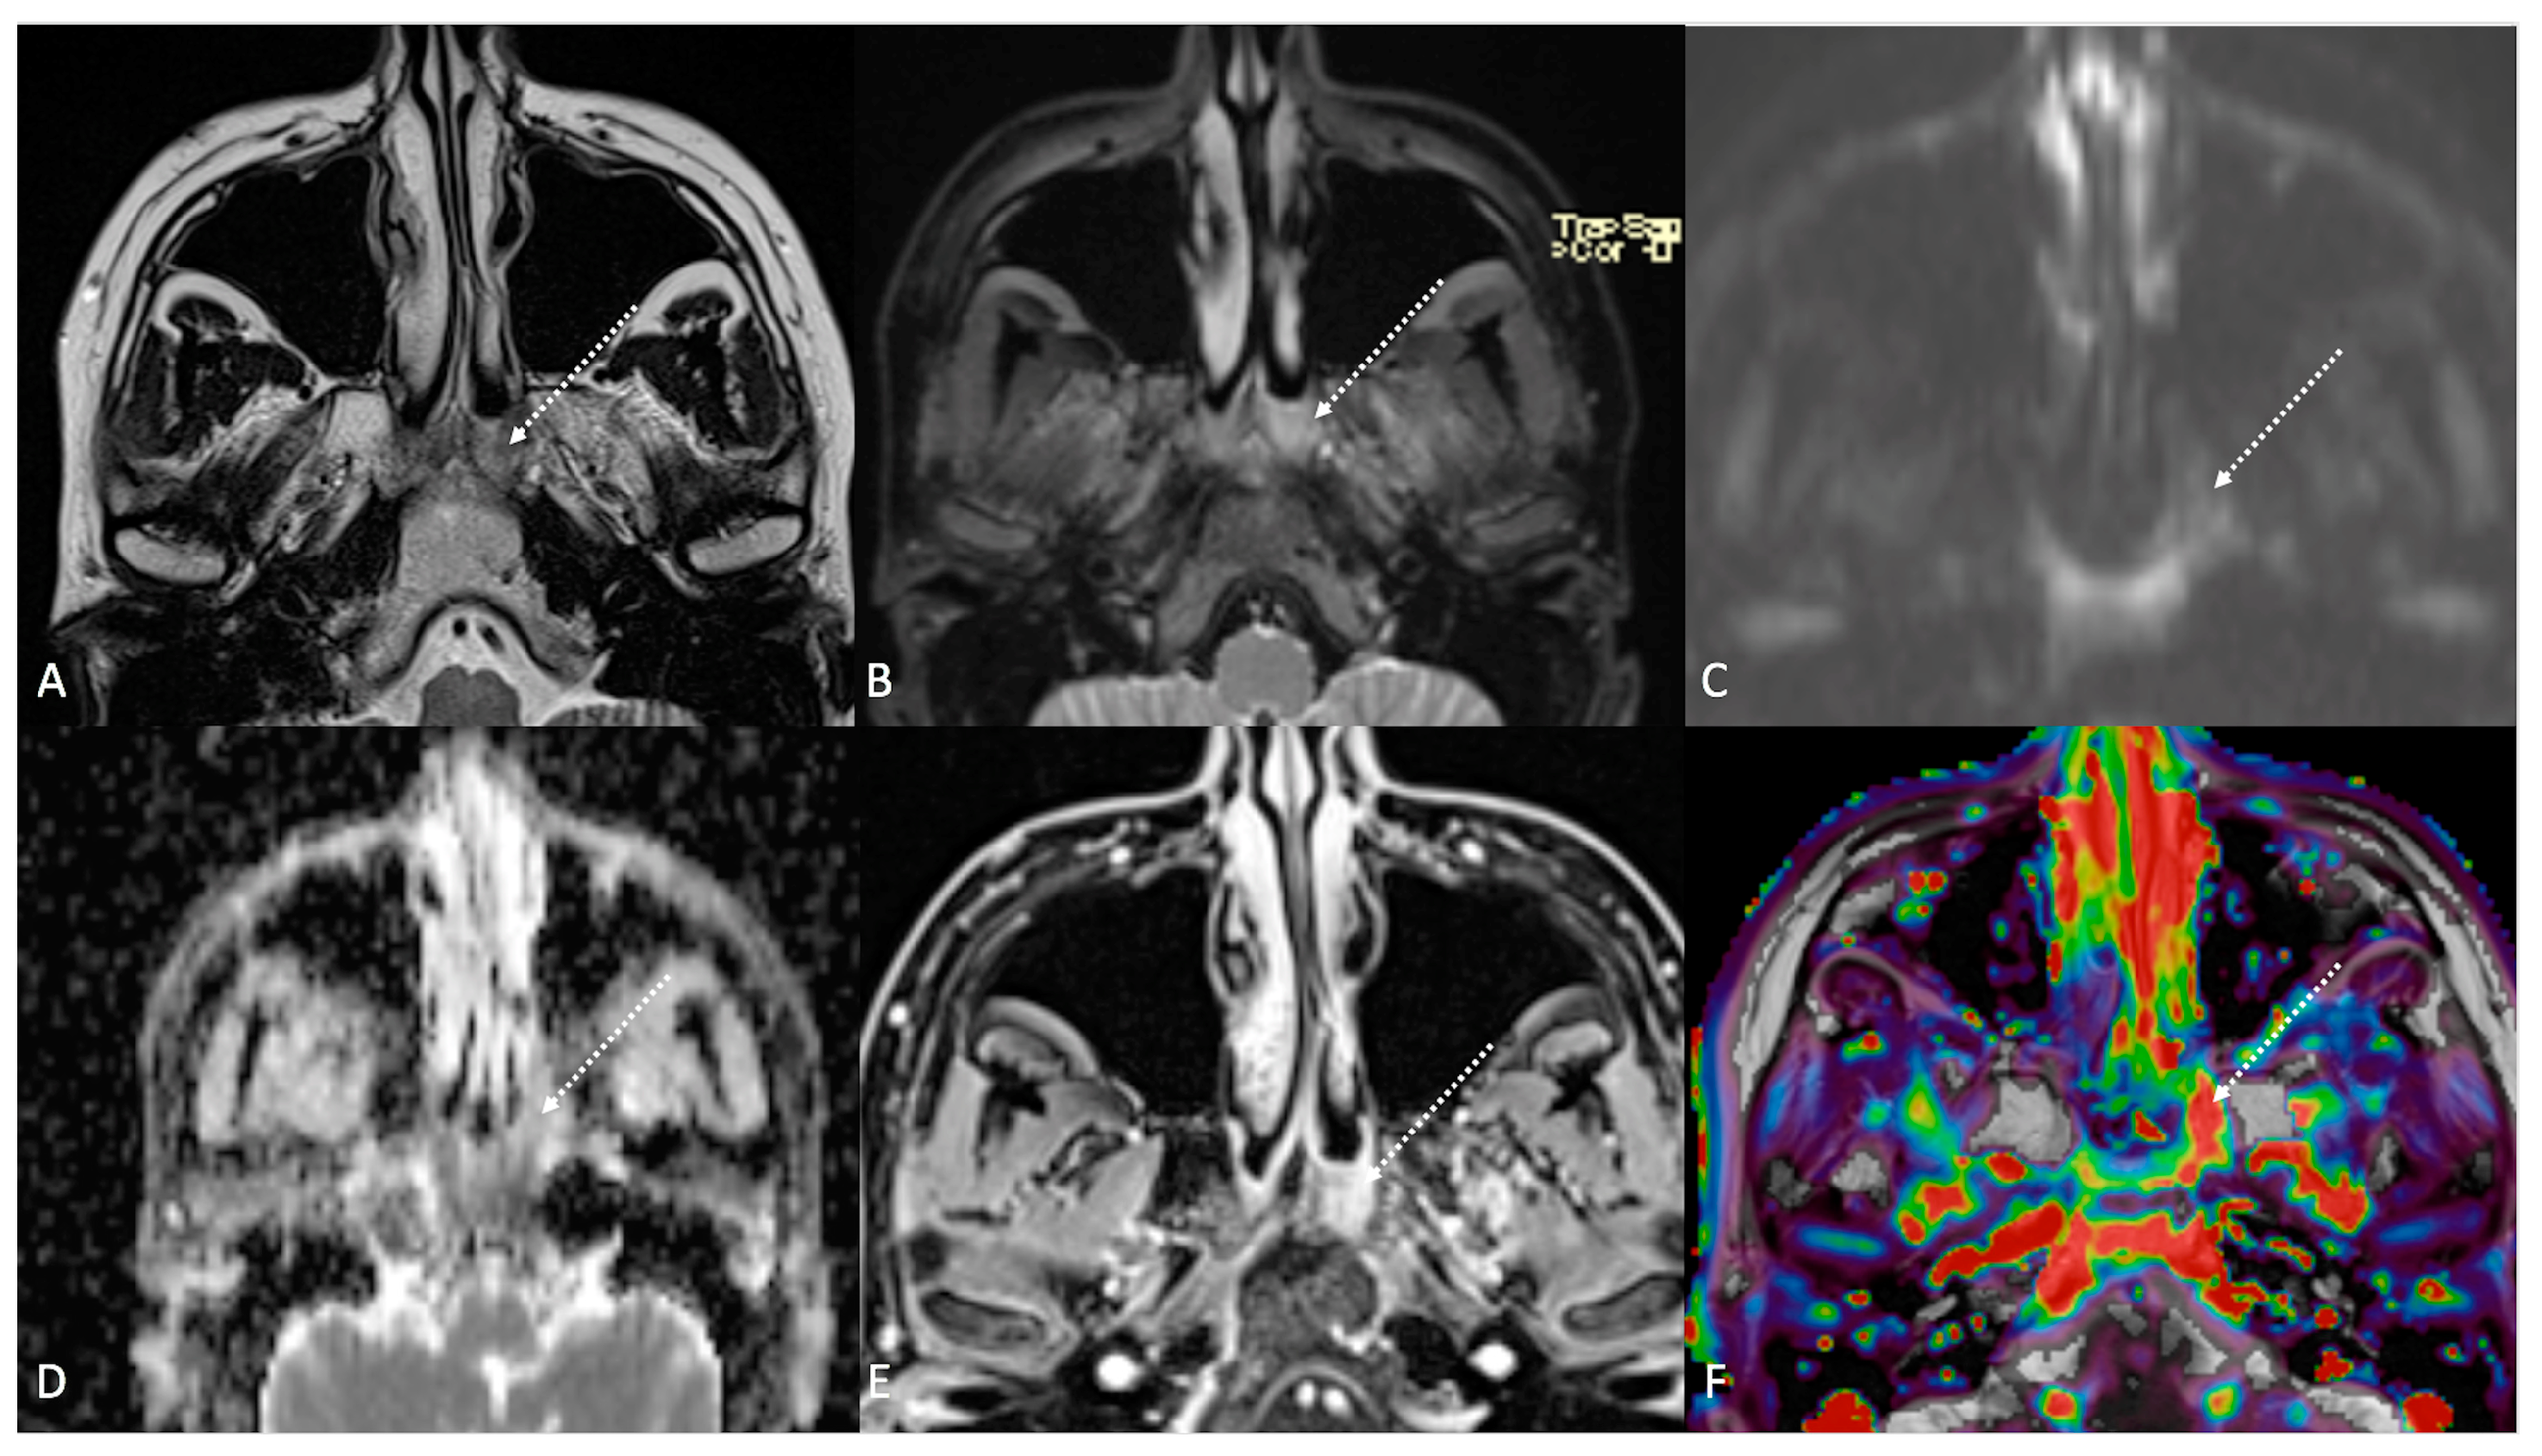

Figure 4.

Post-treatment magnetic resonance imaging (MRI) of a 36-year-old female patient affected by nasopharyngeal carcinoma with left lymph node metastasis (T3N3) and tumoral extension to bilateral Ronsemüller fossa, left nasal choana, and middle skull base, recently treated (3 months before) with chemoradiotherapy (CRT). Early post-treatment MRI demonstrated post-CRT inflammatory residual tissue (white striped arrows) in the left Ronsemüller fossa and ipsilateral nasal choana. Post-CRT inflammatory changes showed hyperintense signal on T2-weighted (A), T2-weighted fat-saturated (B), and diffusion-weighted b800 images (C); high apparent diffusion coefficient value (1.53 × 10−3 mm2/s) (D). After gadolinium contrast agent injection, post-CRT inflammatory residual tissue shows submucosal enhancement of 5 mm thickness (E), and very high K(trans) value (595.25 × 10−3 mm2/s) on dynamic contrast enhancement-perfusion weighted imaging (F). Ratio between K(trans) values of the primitive tumor and residual tissue after CRT, standardized with respect to K(trans) value of the ipsilateral trapezius (K(trans)post/pre/muscle), was 3.17. These findings suggested an increase in capillary permeability caused by CRT.